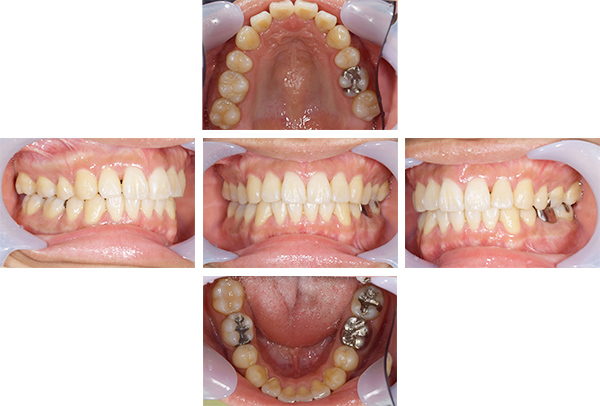

症例写真(治療前)

担当医師所見

治療前:

八重歯が目立ちます。また銀歯もおおく、見た目が気になります。虫歯も散見できます。

レントゲン写真(治療前)

根の治療を3本すでに治療されています。1本根の奥の詰め物が疎になっていますので、根の部分の再治療も行う必要がありそうです。銀歯の中で虫歯になっているものもあります。

治療中

矯正装置をつけています。だんだん八重歯が動いてきているのがわかります。今回のケースでは、抜歯を行わずに矯正ができました。

症例写真(治療後)

治療後:

矯正治療と虫歯の治療すべて終わったときの写真になります。見た目も最初の頃とは全く違いますし、お口の中もすごく綺麗です。

治療

方針

まずは虫歯の治療を行い、被せ物をする部分は仮歯をいれて矯正を行う。矯正終了後、仮歯の部分を最終的な被せ物に変えていく。また気になっていた銀歯もセラミックに変えて終了となった。

内容

セラミックインレー、オールセラミックプレミアム、矯正